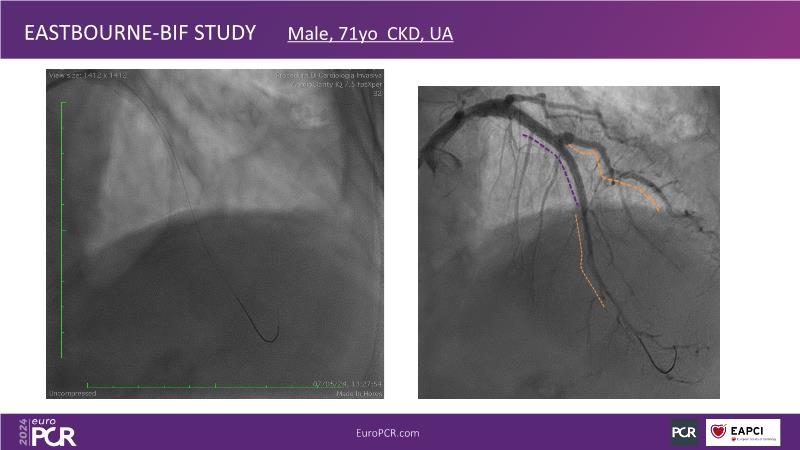

Browse this EuroPCR 2024 session to explore the safety and efficacy of sirolimus-coated balloons from pre-clinical data, review MagicTouch data from real-world populations with case-based examples, and learn about the MagicTouch sirolimus-coated balloon clinical programs. Discover insights and takeaways from the significance of the EASTBOURNE subgroups, and analyze the challenges and opportunities in PCI for diabetic patients.